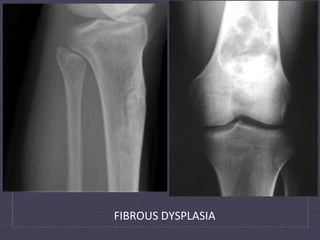

Fibrous  Dysplasia   • Benign  tumour-­‐like  congenital  process   •  Defect  in  osteoblas:c  differen:a:on  and  matura:on,  with   progressive  replacement  of  normal  bone  with  immature  woven   bone   •  Children  and  yound  adults,  <  30  y.o   •  X-­‐Ray  and  CT:  Well  circumscribed  cys:c  or  sclero:c  lesion,   Ground-­‐glass  opacity,  Endosteal  scalloping,  intact  bone   •  MRI:  Heterogenous  Intermediate  signal  T1WI,  heterogenous   low  signal  T2WI   •  Treatment:  no  treatment  à  surgical  decompression

• 28.